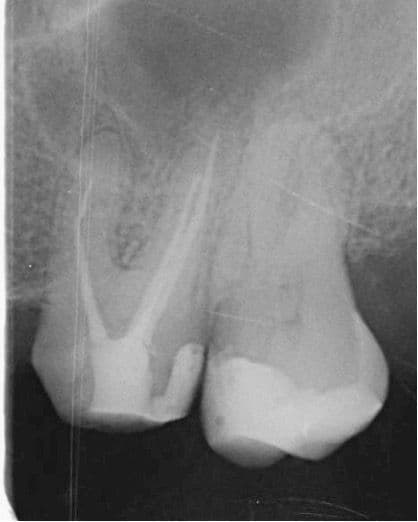

Yaklaşık 9 ay sonra hasta yapılan kontrolde (2024 Şubat) meziobukkal kök ucunda subklinik şekilde seyreden lezyon olduğu görüldü. Ancak hasta mevcut durumda tekrar tedaviyi kabul etmedi (Şekil 3). (Reddetti)

(Şekil 3). 2024 Şubat kontrol meziobukkal kök ucunda periapikal lezyon